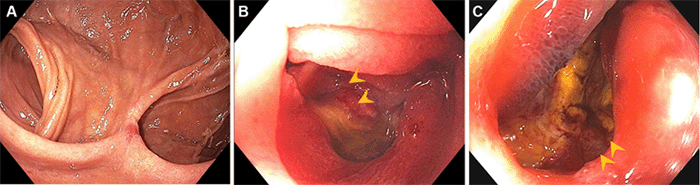

Eight years after surgery, the patient (age 58) presented to the emergency department with severe abdominal pain. Work-up was unrevealing, the symptoms were self-limited, and she was discharged home on a PPI trial, a result which replayed two years later (age 60), with a similar course. It 'was not until sixteen years after surgery (age 66) that the patient was admitted to the hospital with acute-onset, severe, unrelenting epigastric and right upper quadrant abdominal pain associated with bilious emesis, non-bloody diarrhea, focally peritoneal abdominal examination, and worsening leukocytosis and lactatemia, with computed tomography (CT) scan demonstrating segmental jejunal hypoperfusion. She was taken emergently to the operating room for exploration due to concern for bowel ischemia. After extensive lysis of adhesions, findings included a 30 cm segment of dilated and thickened but viable jejunum starting 10 cm proximal to the DJ anastomosis, without evidence of perforation, ischemia, or internal internalization herniation. Upper endoscopy during this hospitalization noted multiple non-bleeding cratered ulcers in the jejunum bordering the DJ, in the efferent more so than the afferent limb (Figure 1). This finding raised concern for gastrinoma recurrence, causing acid hypersecretion and resultant ulcer formation. Given adherent clot, a visible vessel, and concern for bleeding, three clips were placed, although two days later, these dislodged, and the patient had an upper gastrointestinal bleed requiring transfusion. She was managed conservatively and subsequently discharged on a PPI, with plans for outpatient workup of ulcer etiology.

Figure 1. Endoscopy. Published with Permission

A) Diffuse Ulceration at Duodenojejunostomy Anastomosis; B, C) Efferent Jejunal Limb